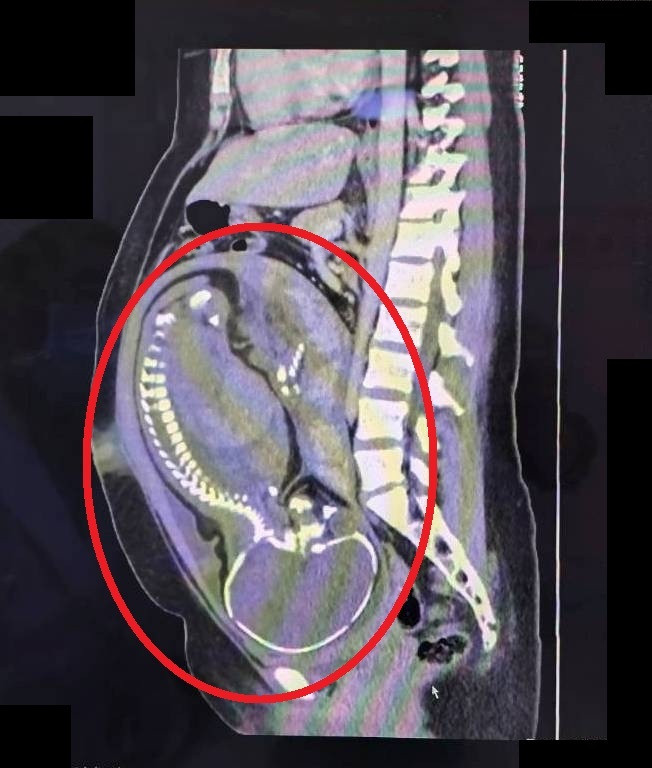

〔記者張勳騰/苗栗報導〕一名26歲懷孕39週的第一胎孕婦,日前因腹痛兩天至苗栗市大千綜合醫院急診就醫,婦產科及一般外科醫師聯合會診,高度懷疑為急性盲腸炎,因此緊急為孕婦執行剖腹生產併盲腸切除手術,手術中發現盲腸已嚴重腫脹化膿,瀕臨破裂邊緣,腹腔內更已有約100毫升的膿樣腹水,情況相當危急,經緊急開刀後,孕婦成功產下健康男嬰,急性盲腸炎經接受抗生素治療,恢復良好、順利平安出院。

大千醫院婦產科醫師林敬旺表示,這名孕婦懷孕期間產檢一切正常,卻在足月前夕發生持續腹痛,檢查發現白血球數值高達18360(正常值約4000-10000)但體溫正常,且無明顯子宮收縮、子宮頸未擴張、胎心音正常,然而腹部觸診時右下腹有明顯壓痛及反彈痛,因此高度懷疑是急性盲腸炎。隨即進行電腦斷層檢查,並會診一般外科醫師劉信誠,共同評估高度懷疑為急性盲腸炎,經與孕婦及家屬充分溝通解釋後,決定執行緊急剖腹生產併盲腸切除手術。